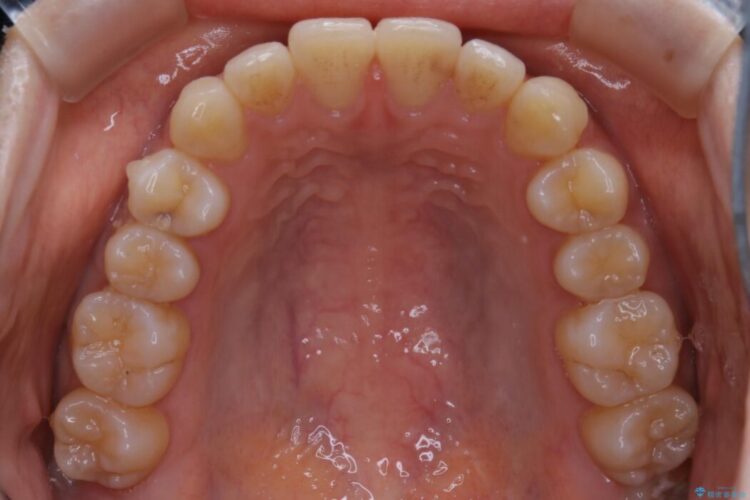

下の前歯のガタつきが気になるとご来院された患者様です。

インビザラインのライトパッケージにて、歯列拡大とディスキング(IPR)をを行いスペースをつくり非抜歯で治療を行いました。

歯列弓の拡大

歯並びが悪くなる原因の一つに「歯列弓の狭窄」というものがあります。

奥歯や前歯が内側(舌側)に倒れ込んでしまったり、歯が生えてくる位置が内側になってしまうことにより歯並びのアーチが狭くなってしまうことを言います。

このような場合、歯並びのアーチを拡大してあげるだけでもガタつきを無くすためのスペースがかなり作れることがあります。